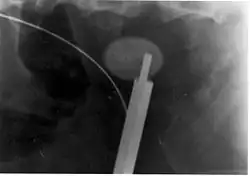

La ureteroscopia se ha vuelto cada vez más popular a medida que los ureteroscopios de fibra óptica rígidos y flexibles se han vuelto más pequeños. Una técnica ureteroscópica implica la colocación de un stent ureteral (un pequeño tubo que se extiende desde la vejiga, sube por el uréter y llega hasta el riñón) para proporcionar un alivio inmediato de un riñón obstruido. La colocación de un stent puede ser útil para salvar un riñón en riesgo de insuficiencia renal aguda postrenal debido al aumento de la presión hidrostática, la hinchazón y la infección (pielonefritis y pionefrosis) causada por un cálculo obstructivo. Los stents ureterales varían en longitud de 24 a 30 cm y la mayoría tienen una forma comúnmente conocida como "doble J" o "doble coleta", debido al rizo en ambos extremos. Están diseñados para permitir que la orina fluya a través de una obstrucción en el uréter. Pueden quedar retenidos en el uréter durante días o semanas a medida que se resuelven las infecciones y a medida que la litotricia extracorpórea o algún otro tratamiento disuelven o fragmentan los cálculos. Los stents dilatan los uréteres, lo que puede facilitar la instrumentación, y también proporcionan un punto de referencia claro para ayudar en la visualización de los uréteres y cualquier cálculo asociado en los exámenes radiográficos. La presencia de endoprótesis ureterales permanentes puede causar molestias mínimas a moderadas, incontinencia de frecuencia o urgencia e infección, que en general se resuelven con la extracción. La mayoría de los stents ureterales se pueden extraer cistoscópicamente durante una visita al consultorio con anestesia tópica después de la resolución de la urolitiasis.